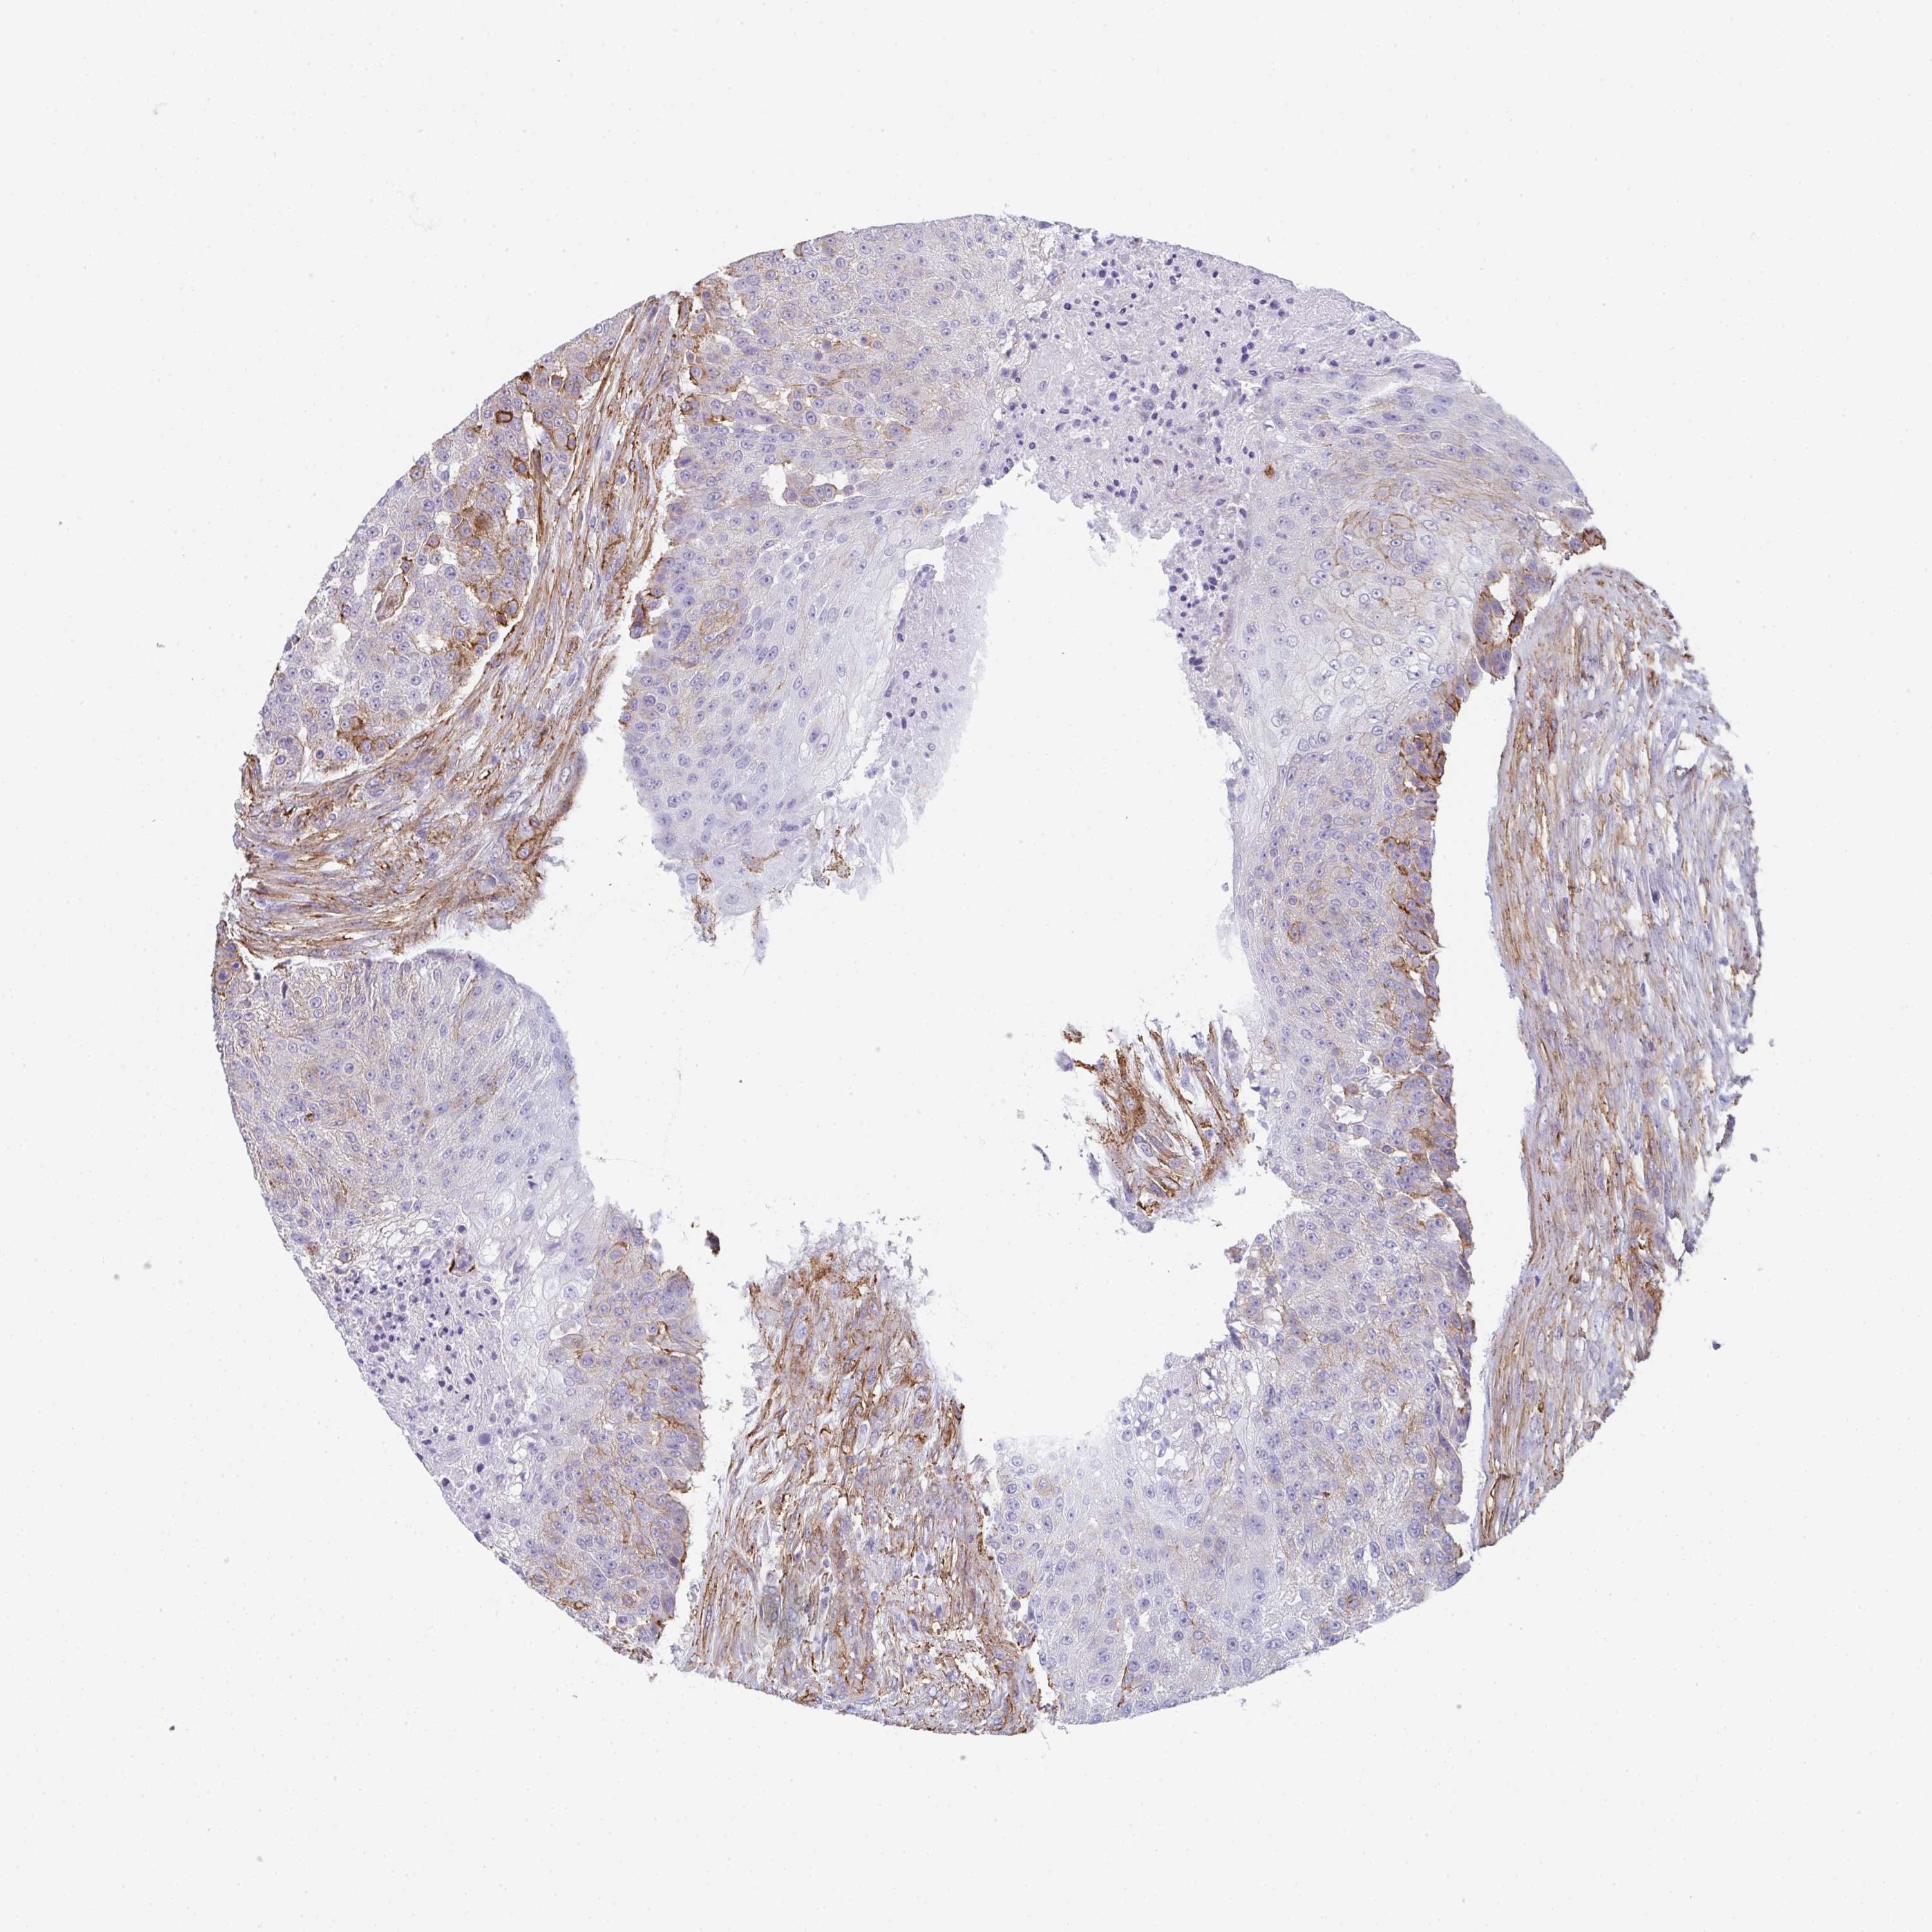

UROTHELIAL CANCER - Protein expressioni

A mouse-over function shows sample information and annotation data. Click on an image to view it in a full screen mode. Samples can be filtered based on level of antibody staining by selecting one or several of the following categories: high, medium, low and not detected. The assay and annotation is described here.

Antibody stainingi

Antibody staining in the annotated cell types in the current human tissue is reported as not detected, low, medium, or high, based on conventional immunohistochemistry profiling in selected tissues. This score is based on the combination of the staining intensity and fraction of stained cells.

Each image is clickable and will lead to virtual microscopy that enables deeper exploration of all samples and also displays staining intensity scores, fraction scores and subcellular localization as well as patient and tissue information for each sample.

Antibody HPA051452

Antibody HPA056940

Staining

High

Medium

Low

Not detected

Intensity

Strong

Moderate

Weak

Negative

Quantity

>75%

75%-25%

<25%

None

Location

Nuclear

Cytoplasmic/membranous

Cytoplasmic/membranous,nuclear

Urothelial carcinoma, Low grade